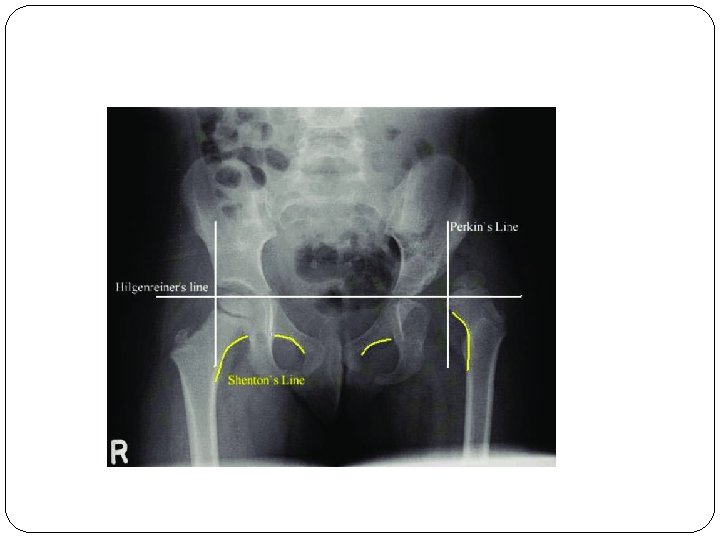

The triradiate cartilage is the 'Y'-shaped epiphyseal plate between the ilium, ischium and pubis to form the acetabulum of the hip bone.